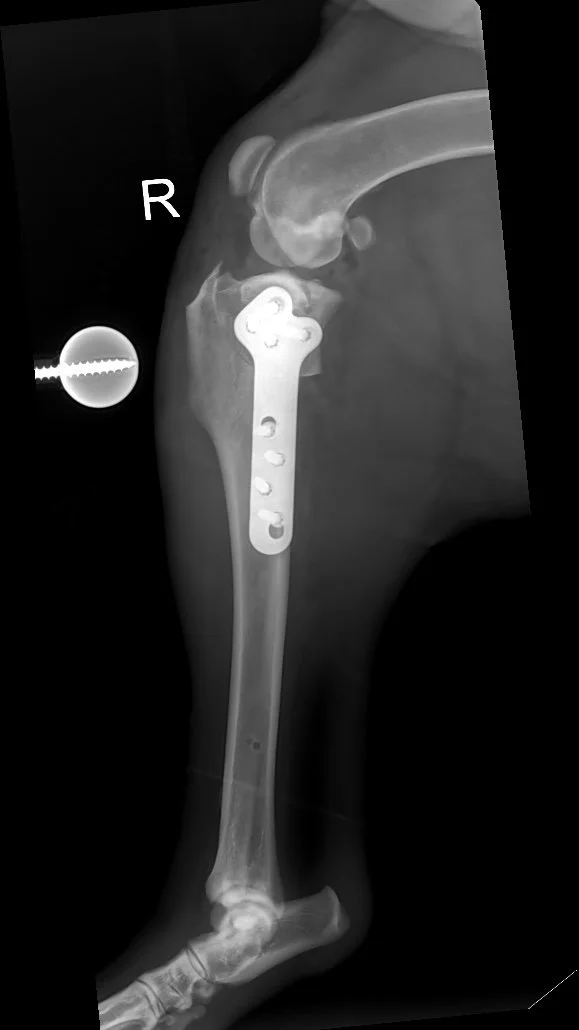

1. Preoperative Assessment: Detailed radiographs are taken to measure the existing angle of the tibial plateau and plan the surgical approach.

2. Surgical Technique: Under general anaesthesia, a curved cut (osteotomy) is made in the top portion of the tibia. This segment is then rotated to achieve a more level orientation, typically aiming for an angle between 5 to 6 degrees.

3. Stabilization: The repositioned bone is secured using a specially designed metal plate and screws, ensuring stability as the bone heals in its new alignment.

Recovery from TPLO surgery typically spans 8 to 12 weeks. During this period, controlled exercise and adherence to postoperative guidelines are essential. Follow-up radiographs are usually performed around 6 weeks post-surgery to assess bone healing. Most dogs regain full function and return to their normal lifestyle and exercise regime once their recovery is complete.